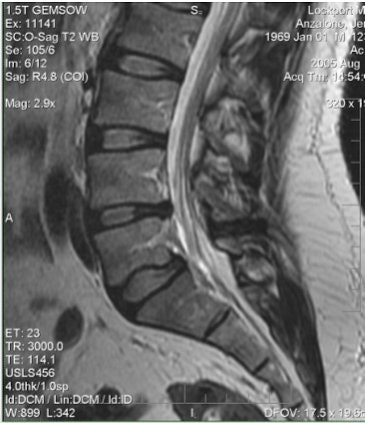

![]() |

| Above and below, axial-load study. L5-S1 anterolisthesis increases from 4 mm to 5 mm with axial loading. L4-L5 retrolisthesis increases from 3 mm to 4 mm with axial loading Mild central spinal canal narrowing. |